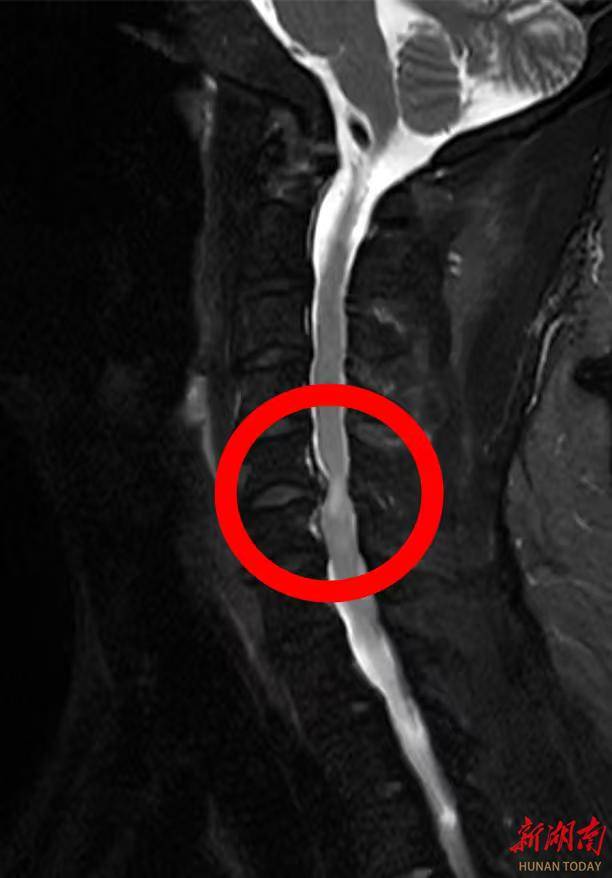

李先生谈及患病经历时满是感慨:“自从得了颈椎病,实在是太痛苦了,颈肩部疼痛,双上肢持续疼痛麻木,让人难以忍受,近期夜间更是因疼痛辗转难眠。”为缓解病痛,他尝试过口服中药、西药、理疗等多种保守治疗,但症状反复发作且逐渐加重,多次求医问诊效果均不理想。经该院脊柱外科团队详细检查,李先生被确诊为“颈椎间盘突出(C5-6节段)伴脊髓压迫”。医生明确告知,若不及时手术,可能导致神经不可逆损伤,甚至出现瘫痪症状,需尽快干预治疗。